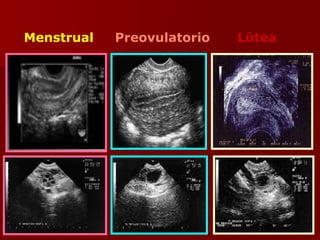

Menstrual Preovulatorio Lútea

Producción Ovárica de

Esteroides Sexuales

Fase Folicular:

Endometrio Proliferativo

1. Se inicia actividad mitótica

de epitelio y estroma

endometrial hacia el 5° día.

2. Aumento de grosor por

hiperplasia glandular y

aumento de sustancia

basal estromática.

3. Glándulas separadas en

superficie.

Fase Lútea

Endometrio Secretor Medio

 5-6 mm de espesor

 Bien vascularizado y rico en

glucógeno

 Glándulas tortuosas con

actividad secretora máxima

 Cambios predeciduales

 Desarrollo de arterias espirales

Apto para la implantación